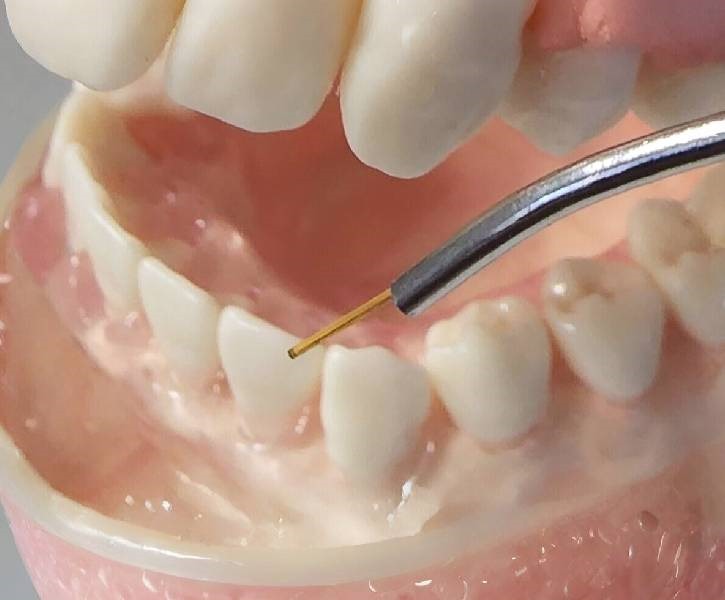

Laser Gum Surgery

Laser gum surgery is a minimally invasive procedure that uses advanced laser technology to treat gum disease and reshape gum tissue. This cutting-edge method ensures precision, faster recovery, and enhanced comfort for patients.